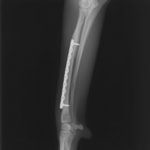

トイプードル 右遠位橈尺骨短斜骨折のALPSによる内固定

Locking Compression Plate

LCPは、スクリュー(ネジ)とプレート(金属の板)をロックする特殊な構造により骨折部位を固定する新しい世代のプレートシステムです。ひとつのホールでロッキングスクリューとスタンダードスクリューの使用を選択できるユニークな構造をしているため、骨折断端間の圧迫を目的とした従来型プレート固定法に加え、高い角度安定性を有するロッキングスクリューを用いた固定法の選択が可能です。従来のプレートシステムでは困難だった部分の骨折や癒合不全の症例に高い治療効果をもたらします。